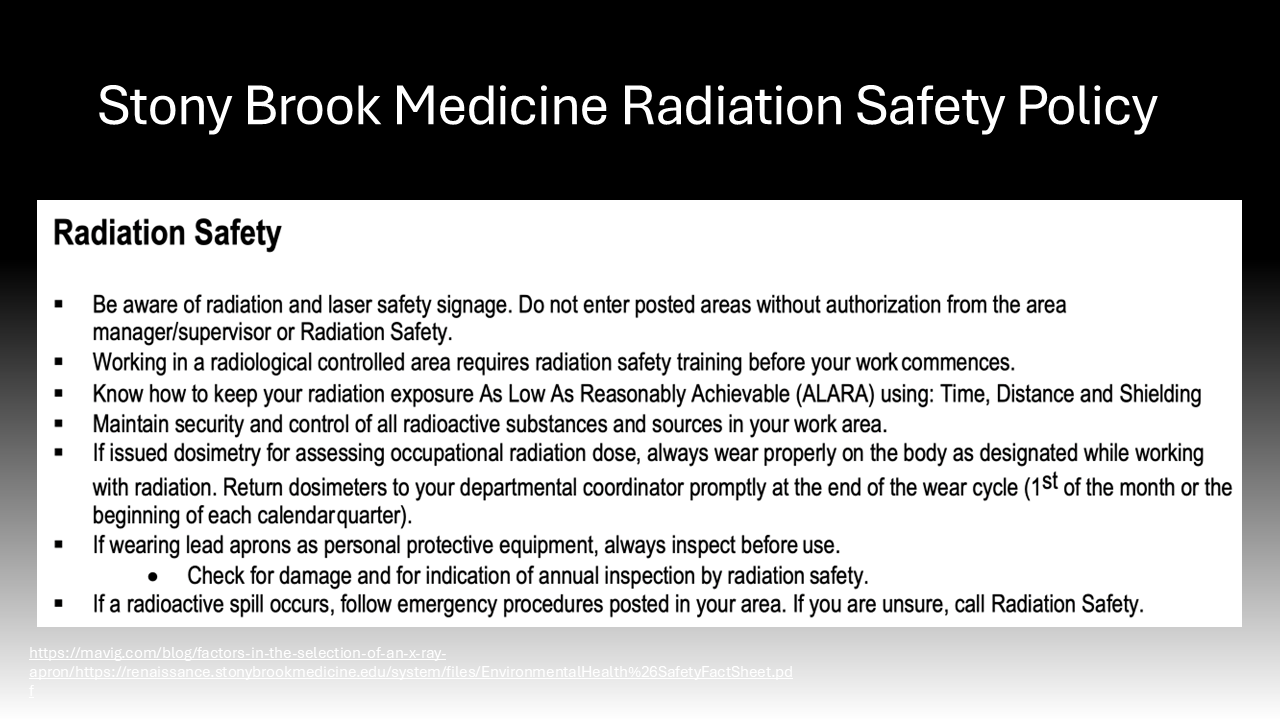

Behavioral modifications and personal protective equipment also play a key role in risk mitigation for those exposed to intraoperative radiation.4 When surgeons stand further away from the radiation source, they are exposed to an inversely proportionally decreased dose of radiation.4 Additionally, simply standing on the same side as the receiver significantly reduces the exposure to the scattering radiation as it bounces off the receiver.4 Following the establishment of the Advisory Committees on X-Ray and Radium Protection in the late 1920s, recommendations and regulations requiring the availability and use of lead protection devices and shielding devices have significantly curbed the negative effects of intraoperative scatter radiation exposure.16 These policies were adopted by the Occupational Health and Safety Administration (OSHA) and local hospitals, such as Stony Brook University Hospital.17–20 Lead aprons can reduce exposure by up to 90%, lead collars can reduce thyroid exposure 9-fold, lead gloves can reduce hand exposure by 75%, lead glasses can reduce exposure by up to 70%, and shields can offer significant reductions.4,21